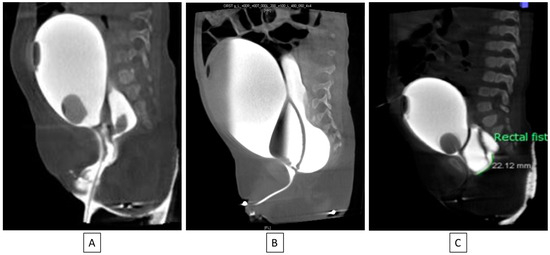

6.9. Cloaca Management

The original cloacal repairs described by Hendren all involved separating the vagina from the urinary tract and reconstructing a neourethra. With the major advance of total urogenital mobilization (TUM), the vagina and urinary tract could be brought down as a unit. Thanks to collaborative teamwork between colorectal and urologic surgery, it became clear that the TUM procedure was only appropriate for a patient with a short common channel (<3 cm) and a long urethra (>1.5 cm). Understanding this distinction is critical to recreating the best possible anatomy for the child and minimizing unexpected changes to surgical plans intraoperatively. For example, if a TUM is performed for a patient with a short urethra (less than 1.5 cm), this would lead to an anatomic situation whereby the bladder neck is left too close to the perineum and below the urogenital diaphragm, leading to urinary leakage. On the other hand, if a TUM is performed in the case of a cloaca with a high confluence (long common channel) and the surgeon finds that the UG sinus does not reach the perineum, then a urogenital separation would be required. Since the anterior urethra would already have been dissected during the TUM, this maneuver can lead to urethral loss. Therefore, it is vital to know in advance the common channel and urethral lengths, which has been made possible by precision cystoscopy and cloacogram imaging [42,43] [Figure 5].

Figure 5. If urethral length is greater than 1.5 cm (A,B), a total urogenital mobilization can be performed; if it is less than 1.5 cm (C), the cloacal repair will need a urogenital separation [40].